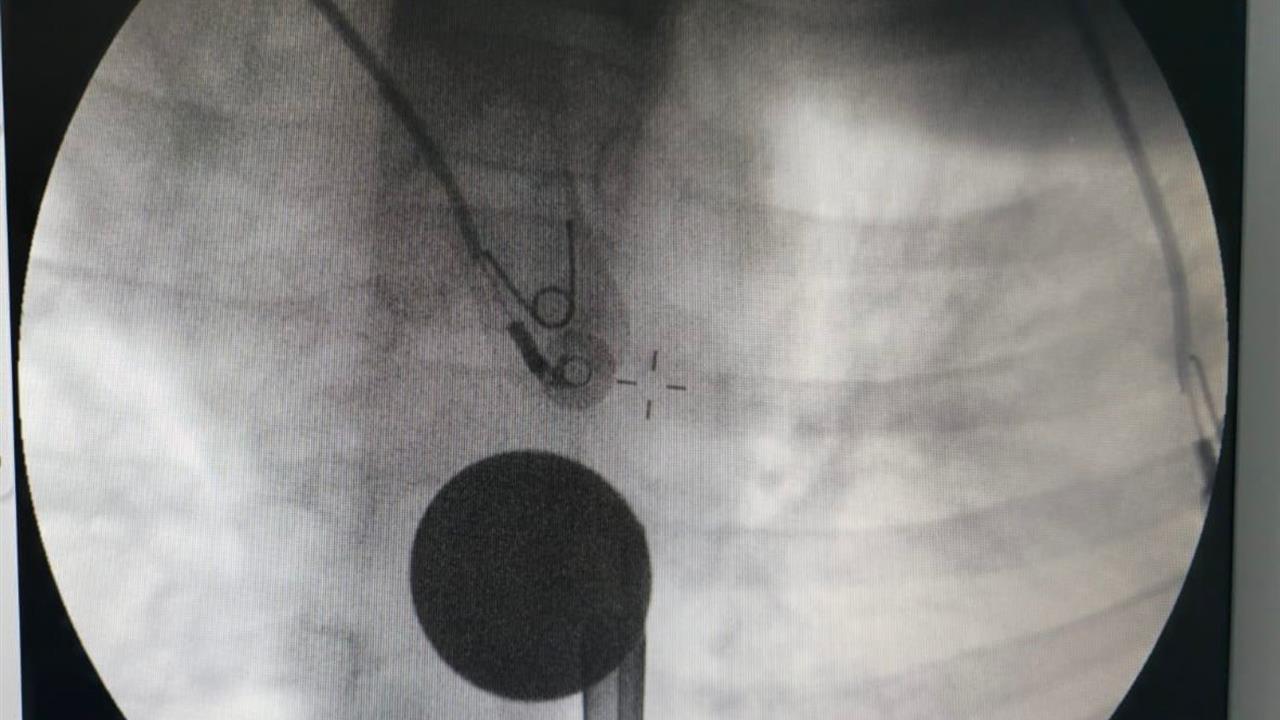

Siirt'te meydana gelen olayda, 8 yaşındaki Y.K., boğazına madeni 5 lira kaçırdı. Ailesi tarafından Siirt Eğitim ve Araştırma Hastanesine getirilen çocuk, yabancı cisim yutma şikayetiyle acil serviste tedavi altına alındı. İlk muayene ve görüntüleme sonrasında, Y.K.'nın yemek borusuna kadar ilerleyen madeni paranın çıkarılması için gerekli müdahaleye başlandı.

Hastane bünyesinde görevli gastroenteroloji uzmanı Dr. Yaren Dirik ile kulak burun boğaz hekimi Yasin Gökçınar, koordineli bir şekilde çalışarak madeni parayı başarılı bir şekilde çıkardı. Yapılan operasyon sonrasında Y.K., bir süre gözlem altında tutuldu ve tedavisinin tamamlanmasının ardından taburcu edildi.

Siirt Eğitim ve Araştırma Hastanesi Başhekim Yardımcısı Uzman Dr. Burak Özkan, çocuklarda yabancı cisim yutma vakalarının ciddiyetine dikkat çekti. Dr. Özkan, "Hastanemize başvuran 8 yaşındaki hastamızın yemek borusuna kaçan madeni para, gastroenteroloji ve KBB ekiplerimizin koordineli çalışmasıyla herhangi bir komplikasyona yol açmadan başarılı bir şekilde çıkarılmıştır. Operasyon süreci sorunsuz geçmiş olup hastamızın genel durumu iyidir," şeklinde bilgi verdi.